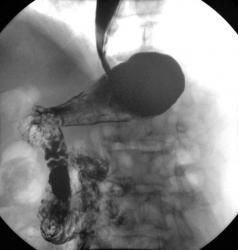

Желудок

Осмелюсь предположить что в антральном отделе желудка есть рак,  инфильтративная форма.

На серии представленных вами снимков сделанных во время скопии, отмечается регидность участка и утолщение слизистой(отмечено стрелками), жалко только  что не была выведена петля 12п.к. в положении стоя, там бы мы увидели четко антральный отдел:

Да это один и тот же больной.Гистологическая верификация-аденокарцинома.И в кишке и в пищеводе дивертикулы.

В антарльном отделе  не толко ригидность ,а стойкое циркулярное сужение.А вот по большой кривизне можно сказать ,что ригидность, хотя контур стенки ровный четкий, но при двойном контрастировании толком не расправился, да и перистальтика почти отсутствует

Протяженность процесса, учитывая зазубренность большой кривизны, надо думать была значительная?

Надо думать, что в антральном отделе, по большой кривизне, имела место быть "чашеподобная" карцинома, со значительным изъязвлением?

Насколько "процесс" распространился на поджелудочную железу?

операции пока не было, однако по данным УЗИ процесс распростраяется на поджелудочную железу по типу инфильтрации.